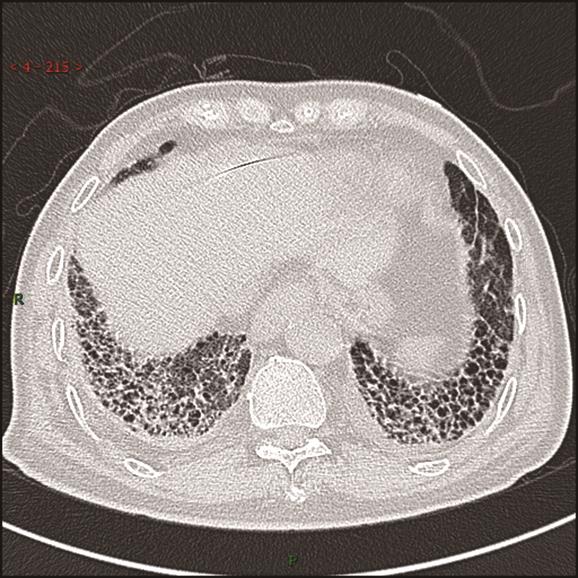

摘要:目的 探究显微镜下多血管炎(microscopic polyangiitis,MPA)肺受累的临床特征与预后因素分析。方法 回顾性分析2014年1月1日至2021年3月1日于重庆医科大学附属第一医院确诊及随访至2022年3月1日的237例MPA肺受累患者临床资料。采用Kaplan-Meier方法和Cox比例风险回归模型分析生存数据,得出累积生存率及预后因素。结果 MPA肺受累患者的平均年龄是65.18岁,中位随访时间为26.13个月。在纳入研究的237例患者中,MPA伴弥漫性肺泡出血(diffuse alveolar haemorrhage,DAH)患者98例(41.35%)。MPA肺受累患者1年、3年、5年累积生存率分别为67.50%、54.10%、43.00%。中位生存时间为45.03(0.10,97.73)个月。MPA伴DAH患者1年、3年、5年累积生存率分别为63.30%、49.40%、40.20%。Cox多因素回归分析显示年龄>65岁(HR=1.981,95%CI=1.244~3.154,P=0.004)、白细胞总数(white blood cell,WBC)>10×109个/L(HR=1.860,95%CI=1.170~2.956,P=0.009)、血清肌酐(serum creatinine,sCr)>250 μmol/L(HR=1.987,95%CI=1.217~3.243,P=0.006)、氧合指数<300 mmHg(HR=2.780,95%CI=1.696~4.557,P<0.001)、诊断时第三版伯明翰血管炎活动性评分(Birmingham vasculitis activity score version 3,BVASv.3)(HR=1.040,95%CI=1.006~1.075,P=0.020)是影响患者生存时间的独立预测因素(P<0.05)。结论 MPA肺受累患者生存率低下,年龄>65岁、WBC>10×109个/L、sCr>250 μmol/L、氧合指数<300 mmHg、诊断时BVASv.3是MPA肺受累预后不良的独立危险因素。